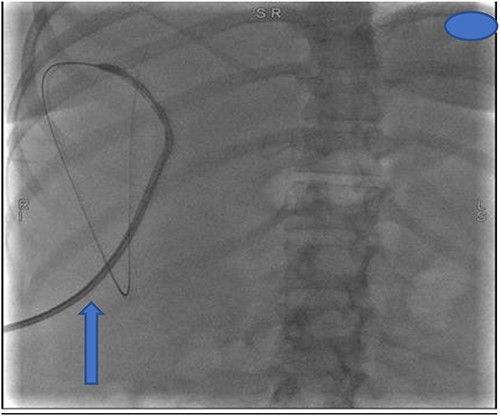

The following day, percutaneous drainage of the biloma was done through a pigtail catheter inserted through sub phrenic space access (Fig. 3). Subsequently after 6 days, drainage amount of the biloma markedly decreased and catheter was removed on the seventh day after insertion. The patient had marked symptom improvement afterwards, and control abdominal US was normal.

Insertion of percutaneous catheter drainage for drainage of biloma.